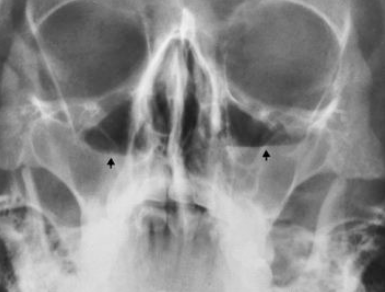

PT presents with toothache and has recently fallen ill with a viral infection

What pathology is present?

sinusitis (image demonstrates chronic sinusitis as mucosal lining has gotten polyp-like, thus no visualization of air-fluid levels)